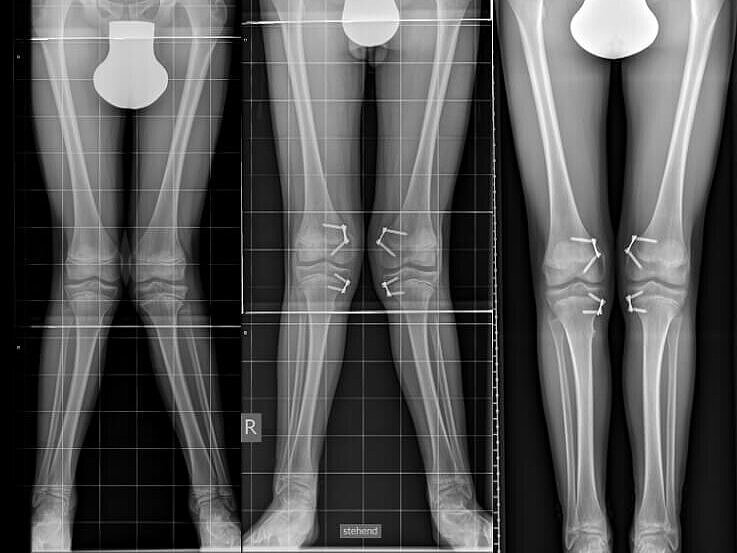

Wachstumslenkungen

Manchmal können bei Kindern Wachstumslenkungen jeglicher Art bei O-Beinen, X-Beinen oder Beinlängendifferenzen mit Fehlstellungen ihrer Beine auftreten.

Um dies zu korrigieren ist in der Regel ein kleiner operativer Eingriff notwendig, um die gewünschte Korrektur zu erreichen. Die Behandlungsdauer variiert je nach Schweregrad der Fehlstellung und kann zwischen 6 und 24 Monaten betragen.